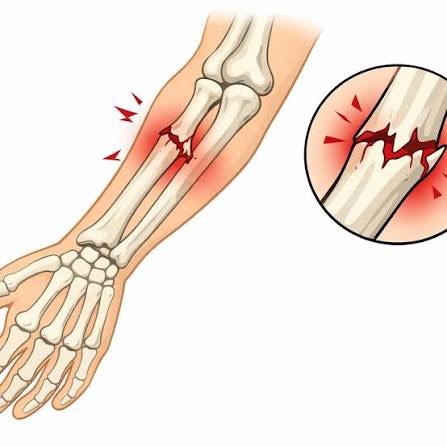

Suyak sinishlarini davolash

Barcha turdagi suyak sinishlarini zamonaviy usullar bilan davolash

Bloklovchi intramedulyar osteosintez

Operatsiyadan keyingi kuniyoq yura olasiz

Tashqi osteosintez

Ochiq sinishlarda

Teri kesmalarisiz osteosintez

Yopiq repozitsiya va osteosintez

Mini invaziv osteositez